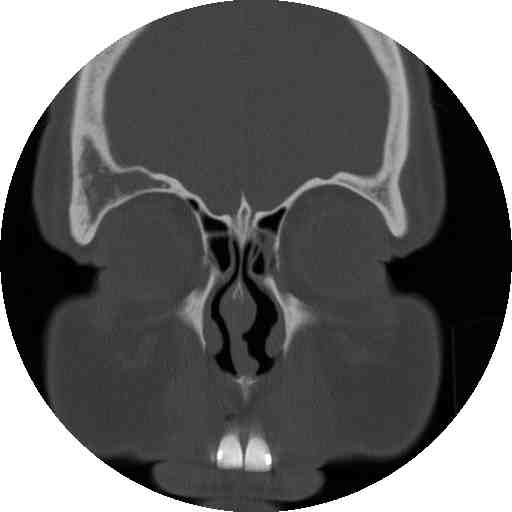

What type of image is it? CT scans or MRI scans (T1 or T2

weighted)

Which plane the image is in? axial, sagittal or coronal.

Describe the image: In ophthalmology, most of the pathology will

be focused on the globe, orbit or the brain. If it were the viva,

ask the examiner for some history.

Examine the following strucutres in order and always compare the

two sides for asymmetry(ies):

globe: eye present (enucleated eye or implant)?

lens present (aphakia)? opacities in the vitreous (blood or foreign body)?

calcification in the retina (retinoblastoma)? calcification in the optic

nerve (drusen)? any abnormal thickening of the sclera (compared with the

opposite eye, thickening suggests scleritis)?

extraocular muscle enlargement (the main differetial

diagnosis include: thyroid eye disease if tendon is not involved or myositis

if the tendon is involved; other possibilities include neoplasm either

primary or secondary)?

space occupying lesion in the orbit: lacrimal

fossa (lacrimal gland tumour)? intraconal lesion (optic glioma, capillary

haemangioma or optic nerve meningioma)? diffuse lesion (lymphoma, metastatic

tumour or acute infection or inflammation)? dilated superior ophthalmic

vein (carotid-cavernous fistula)?

bony lesion: localized bony expansion (meningioma

and osteoma in which the lesions have the same density as the surrounding

bone; fibrous dysplasia in which the bone density is reduced)? any bony

thinning next to an orbital lesion (suggesting long-standing chronic lesion)?

any lytic lesion (suggesting malignant lesions such as metastasis or myeloma)?

brain lesion (enlarged pituiary fossa suggests

pituitary tumour, wedge-shaped hypodense area suggests cerebral ischamia;

wedge-shaped hypodense area suggests cerebral haemorrahge)?